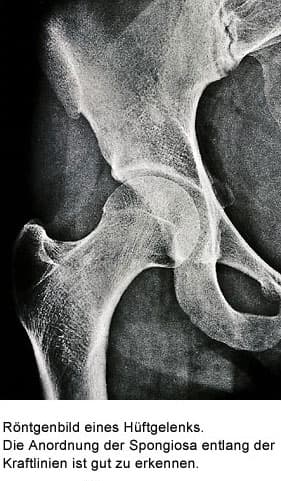

Knochen liegt in zwei verschiedenen Strukturen vor. Der kompakte Knochen, die „Compakta“, bildet die harte Röhre z.B. des Oberschenkel-Knochens. Der netzartige Knochen, die „Spongiosa“, liegt im Inneren der Kompakta, und zwar im Bereich der Knochenteile, welche die Gelenke bilden, und in den Wirbelkörpern.

Die Spongiosa stützt die Gelenkflächen ab und überträgt die auftretenden Kräfte auf die Kompakta. Die geometrische Anordnung der Spongiosa folgt den Kraftlinien, die durch ein Gelenk wirken. Diese Kraftlinien werden Trajektorien genannt. Die gesamte Knochenmasse besteht etwa zu 80% aus Kompakta und zu 20% aus Spongiosa.